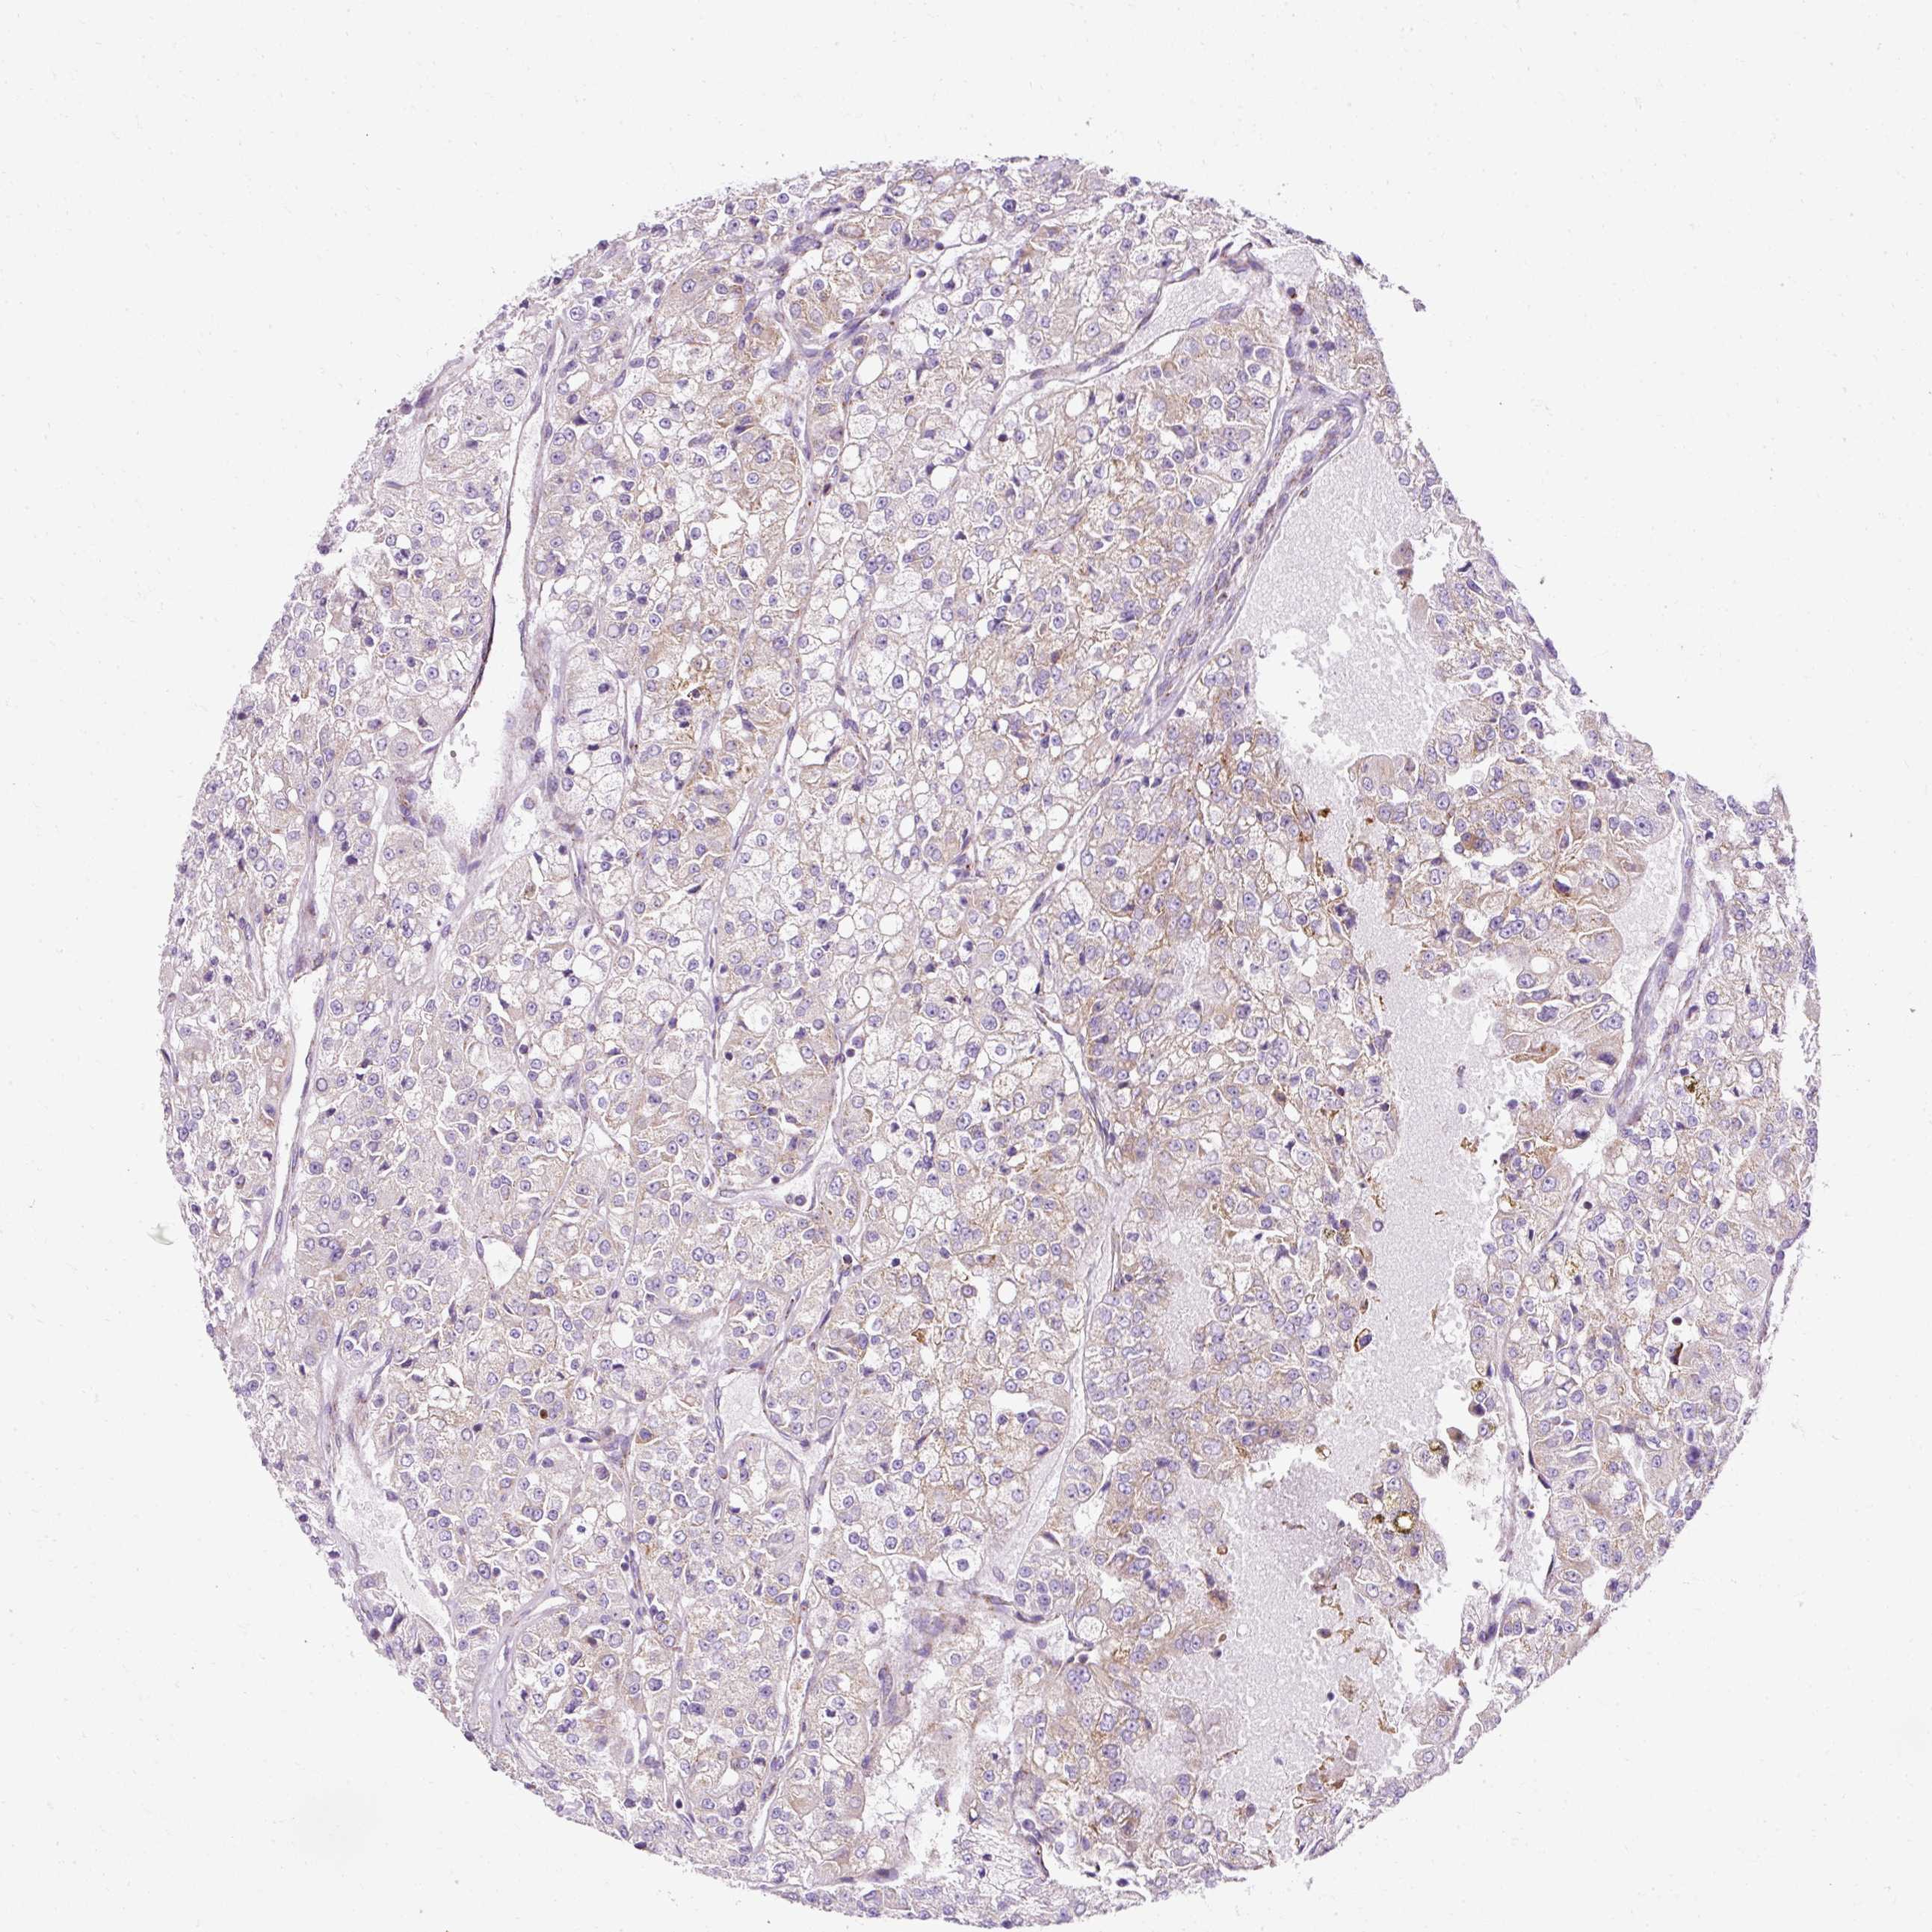

Renal cancer

Kidney renal clear cell carcinoma